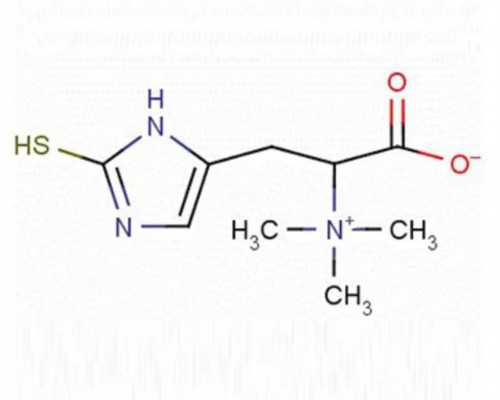

2026如何增强Y染色体活力?科学调理与助孕生儿子攻略

想知道2026年如何增强Y染色体活力吗?本文为您提供科学的调理方案,通过饮食与生活方式的优化,助力高龄生子家庭提升生儿子几率,实现优生优育。